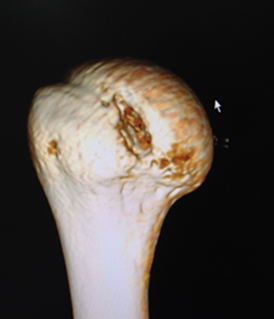

肩关节Bony-Bankart损伤

肩关节镜下缝合修复Bony-Bankart术后